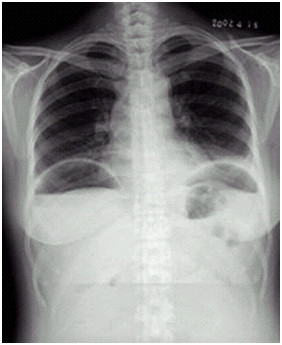

04卷-4.病史:女性,42歲,腹痛1天,進(jìn)行性加重。診斷(本題滿分2.00分)

A.腸梗阻

B.腸結(jié)核

C.正常腹平片

D.消化道穿孔

本題答案:D

【該題針對“ X線-消化道穿孔 ”知識點(diǎn)進(jìn)行考核】